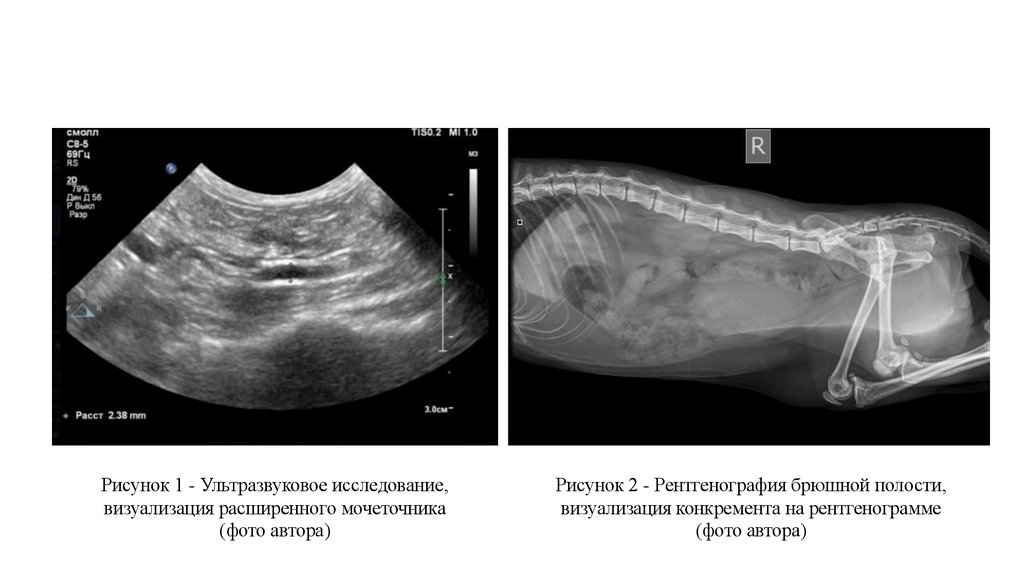

Рисунок 1 - Ультразвуковое исследование,

визуализация расширенного мочеточника

(фото автора)

Рисунок 2 - Рентгенография брюшной полости,

визуализация конкремента на рентгенограмме